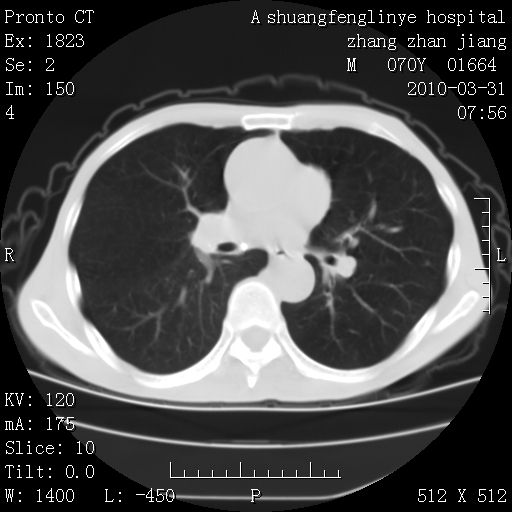

标题: CT25450:肺结核?

双上肺继发型tb并左上空洞形成,主动脉冠脉钙化。

支持:继发性肺结核伴空洞形成!建议纤支镜检查待出外周围型肺癌可能!

1)两肺上叶继发性肺结核并左肺上叶空洞形成。2)冠状动脉及主动脉钙化。